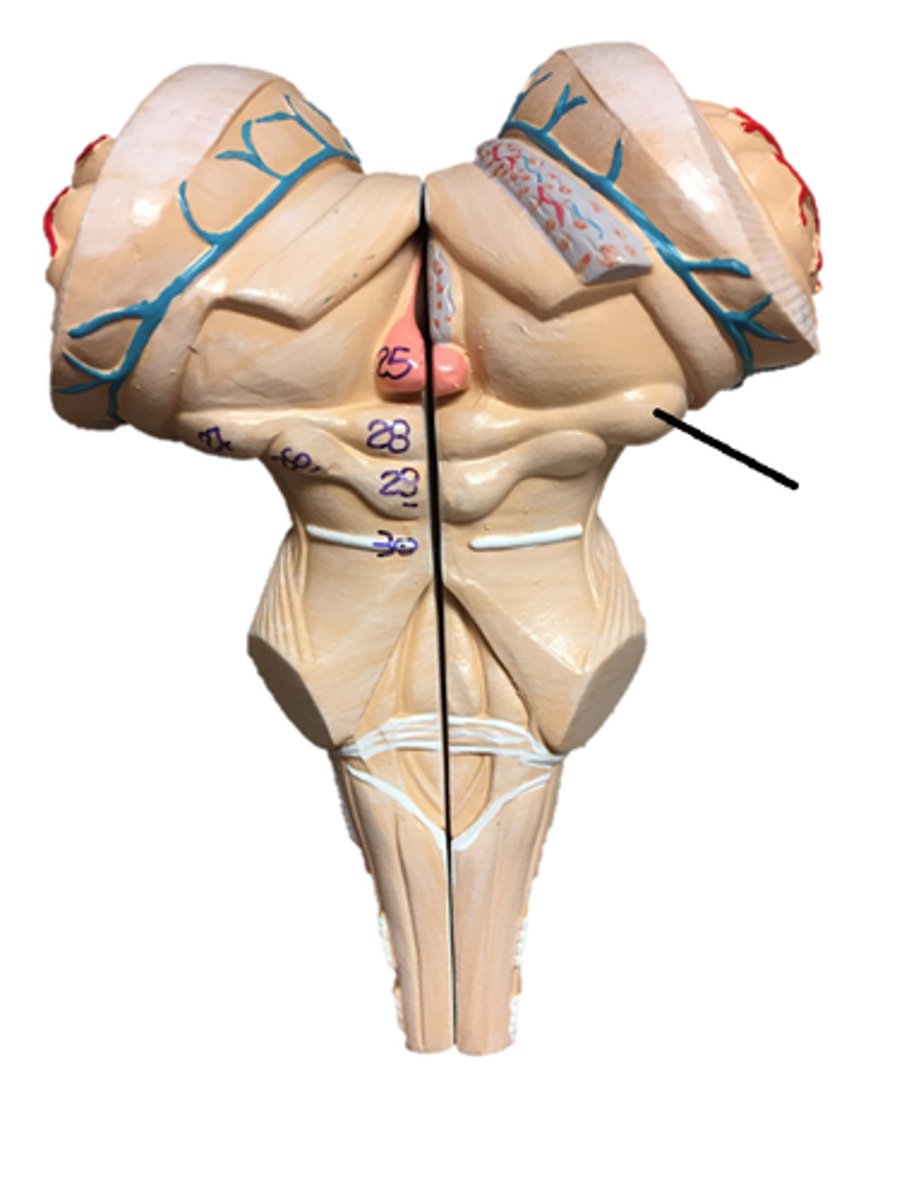

pons

midbrain

medulla oblongata

olive

superior colliculi

inferior colliculi

cerebral peduncles

vermis

cerebellar peduncles